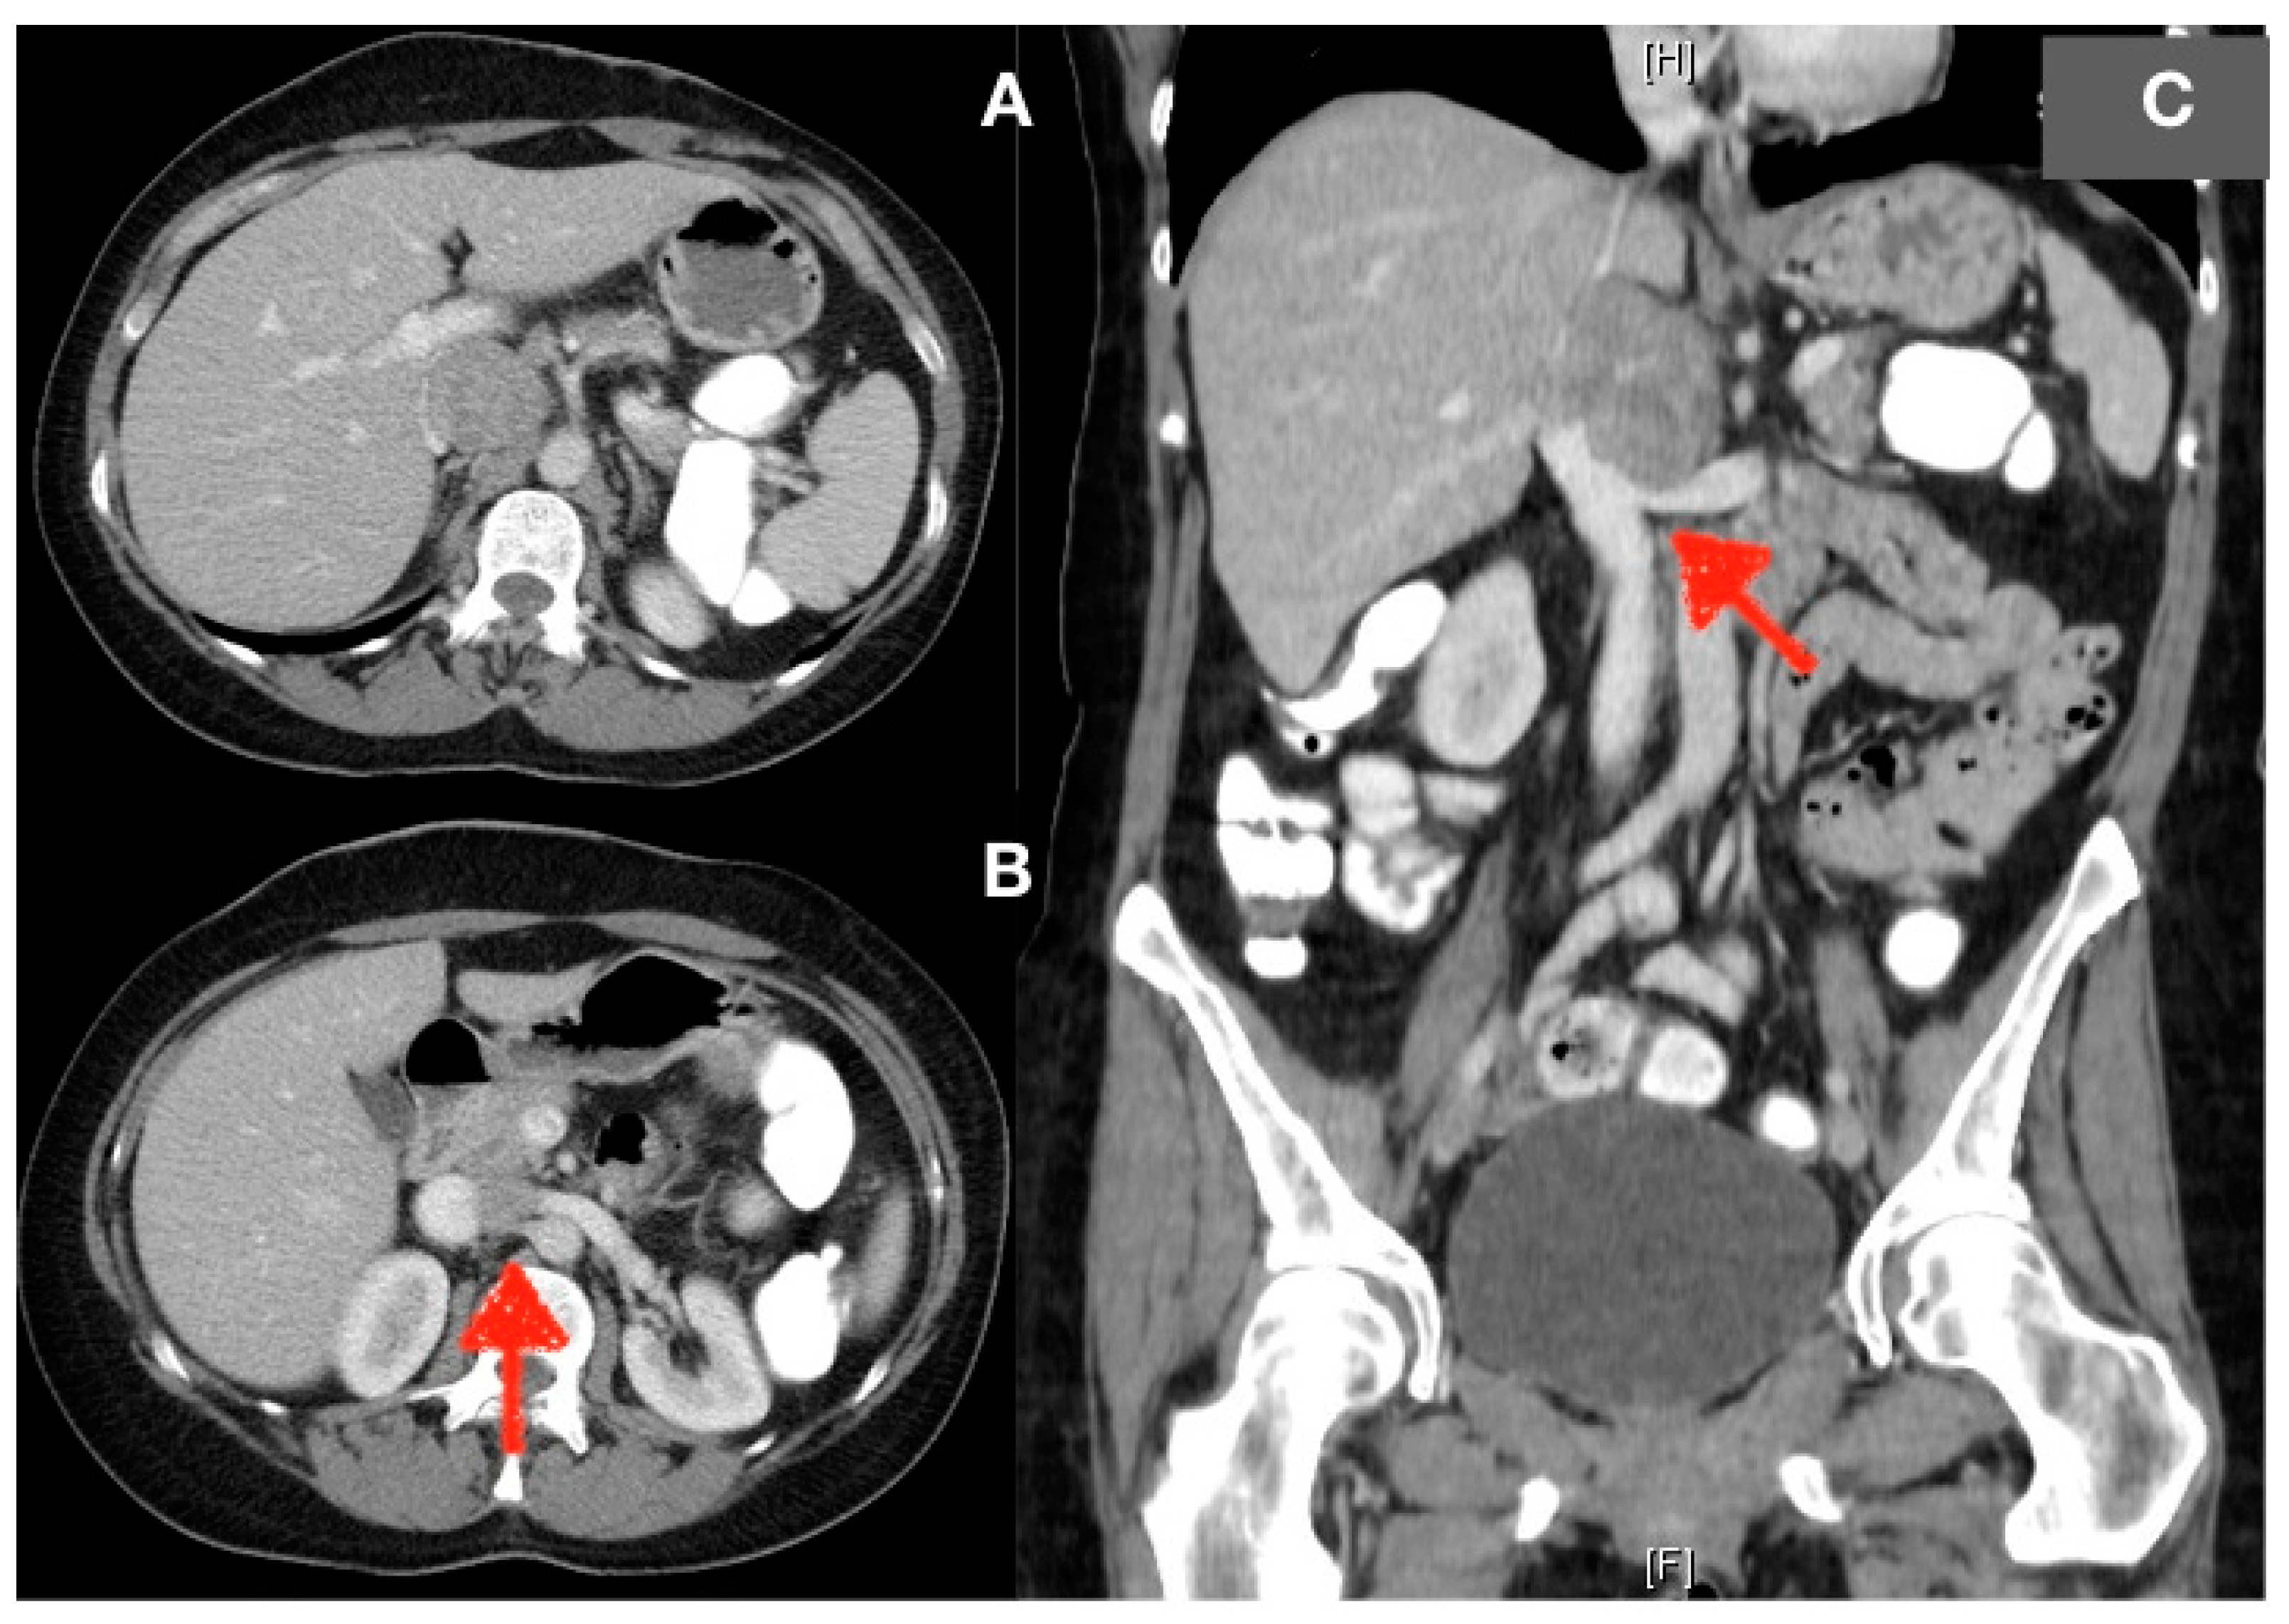

Diagnostic management included establishment of a medical history, performance of clinical examination and imaging tests, including an abdominal ultrasound and computerized tomography (CT) scan to confirm the tumor origin and growth, as well as infiltration, if any, of adjacent structures. Positron emission tomography (PET) CT scan and abdominal magnetic resonance imaging (MRI) were additionally used for diagnosis. In cases with known IVC involvement preoperatively, an angio-CT and vascular reconstruction were performed to assess the level of involvement, as well as the extent and development of collateral circulation or not. These imaging tests also allowed us to rule out distant metastases, and to assess resectability and the option for vascular reconstruction (Figure 1). In some cases, the decision to resect the IVC was made during surgery, because IVC involvement was an intraoperative finding, which had remained unknown up to that point. Preoperative investigations included complete blood and liver function test as well as routine anesthetic and cardiorespiratory evaluation. In the preoperative planning phase, an electrocardiogram was conducted for all patients. In cases where inferior vena cava resection was already known to be necessary, a transthoracic echocardiogram was performed.

Figure 1.

(A) CT image showing a lesion within the inferior vena cava with displacement of the hepatic hilum. (B) Axial section: opening of the left renal vein into the inferior vena cava (red arrow) is interrupted. (C) Coronal section: showing broad contact (red arrow) of the mass with the left renal vein without interrupting flow. The images correspond to patient number 12. As can be observed in the image, the lesion is identified in the region below the supra-hepatic veins. In this patient, a circumferential resection of the inferior vena cava was performed with replacement with a Goretex prosthesis. The patient exhibited no postoperative complications.